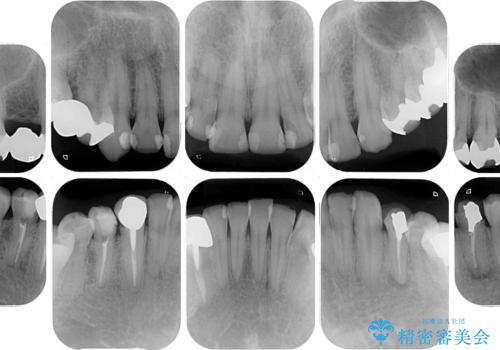

- 近医にて下顎奥歯の抜歯が必要と言われたとのことで来院された患者様です。

診察の結果、奥歯は左右ともに抜歯が必要な状態でした。

抜歯が必要な歯は事前に抜歯をし、その後ワイヤー装置にて歯列矯正を行い、途中でインプラントを埋入し、オールセラミッククラウンにて補綴治療を行うこととしました。